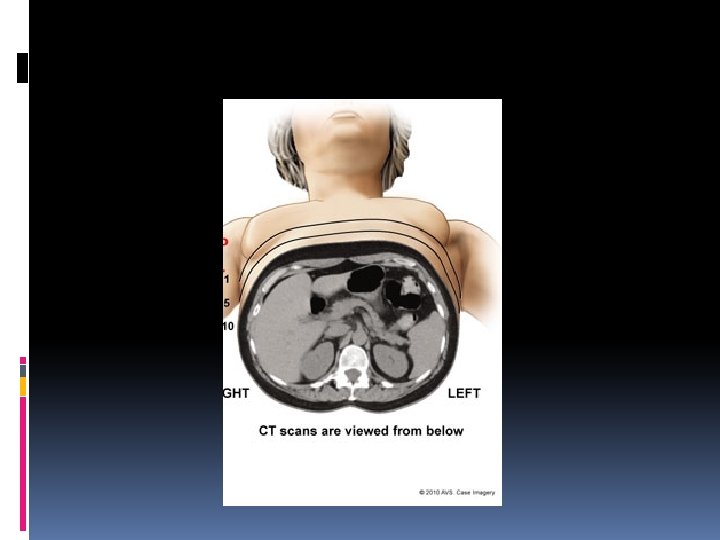

5 2 1 6 4 3

5 2 1 6 1 - Rectum 2 -Sigmoid colon 3 -Descending colon Transverse colon 6 -Cecum 4 3 4 -Ascending colon 5 -